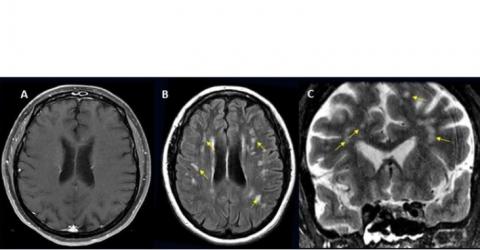

- les complications les plus fréquentes comprennent l'accident vasculaire cérébral ischémique (AIT), avec une incidence de 6,2 %, suivi par l'hémorragie intracrânienne (3,72 %) et l'encéphalite (inflammation du cerveau) (0,47 %) ;

- certaines complications cérébrales rares sont également identifiées telles que l'encéphalomyélite aiguë disséminée (ADEM), une inflammation du cerveau et de la moelle épinière et le syndrome d'encéphalopathie postérieure réversible (SEPR), un syndrome qui induit de nombreux symptômes similaires à ceux de l’AVC ;